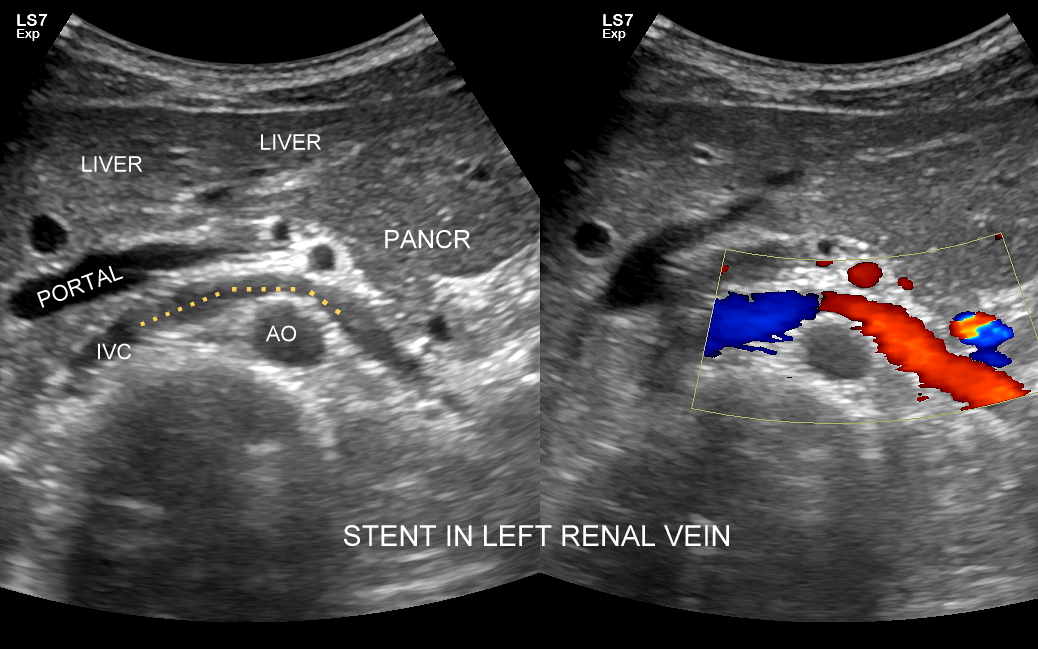

Badanie USG żył kończyn dolnych najczęściej wykonywane jest w ramach diagnostyki niewydolności żył powierzchownych oraz ich objawów w postaci pajączków żylnych, żylaków kończyn dolnych, obrzęków i owrzodzeń żylnych. Kolejnym pod względem częstości wskazaniem do badania Doppler żył jest podejrzenie zakrzepicy żył głębokich kończyn dolnych, monitorowanie leczenia zakrzepicy oraz ocena jej powikłań odległych. Powikłaniem nieleczonej zakrzepicy żył głębokich może być zespół pozakrzepowy manifestujący się masywnymi obrzękami kończyny i zaburzeniami troficznymi. Badanie USG Doppler żył kończyn dolnych często uzupełniane jest oceną układu żył centralnych w miednicy i jamie brzusznej. W tych obszarach również pojawiać się mogą żylne zmiany zakrzepowe, niedrożności żył, a nawet zmiany nowotworowe.

Podczas najczęściej przeprowadzanego badania, tj. USG Doppler kończyn dolnych, oceniane są żyły głębokie oraz powierzchowne na całej długości kończyny – od stóp aż do pachwiny. Czasami mogą zaistnieć wskazania do rozszerzenia badania na wyższy poziom układu żylnego, tj. na żyły biodrowe w miednicy i żyłę główną dolną w jamie brzusznej. Badanie USG żył jest badaniem dynamicznym, tzn. oprócz oceny wyglądu żył wykonuje się różnorodne próby czynnościowe, takie jak kompresja, głębokie oddychanie, próba Valsavy, podczas których rejestruje się przepływy krwi w żyłach.

Interdyscyplinarna Pracownia USG dr Tomasza Szczepańskiego to instytucja przełomowa na gruncie Polski i Europy. W ramach jej działania od 2011 r. wprowadzonych zostało do polskiej medycyny wiele innowacyjnych rozwiązań, w tym badania MPUS jamy brzusznej, USG wątroby z kontrastem CEUS, USG skóry i tkanek miękkich, USG twarzy, a także kompleksowy przegląd zdrowia realizowany przy użyciu zaawansowanego technologicznie sprzętu USG. Dr Szczepański umożliwił mieszkańcom Wrocławia dostęp do pełnej gamy badań dopplerowskich, w tym badania USG narządów przeszczepionych. Jako pierwszy w Polsce wykonał śródoperacyjne badanie CEUS przy operacji nerki. Sprawdź więcej:

USG PRZEPŁYWY NERKOWE >